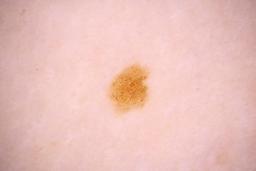

ISIC_8336318

Clinical

| Field | Value |

|---|---|

| age_approx | 40 |

| anatom_site_1 | Trunk |

| anatom_site_2 | Anterior trunk |

| anatom_site_3 | Anterior abdomen |

| clin_size_long_diam_mm | 6.19 |

| diagnosis_1 | Malignant |

| diagnosis_2 | Malignant melanocytic proliferations (Melanoma) |

| diagnosis_3 | Melanoma Invasive |

| diagnosis_4 | Melanoma Invasive, Superficial spreading |

| diagnosis_confirm_type | histopathology |

| image_manipulation | instrument only |

| image_type | TBP tile: close-up |

| lesion_id | IL_5097969 |

| mel_thick_mm | 0.40 |

| patient_id | IP_8989787 |

| sex | male |

| tbp_tile_type | 3D: white |